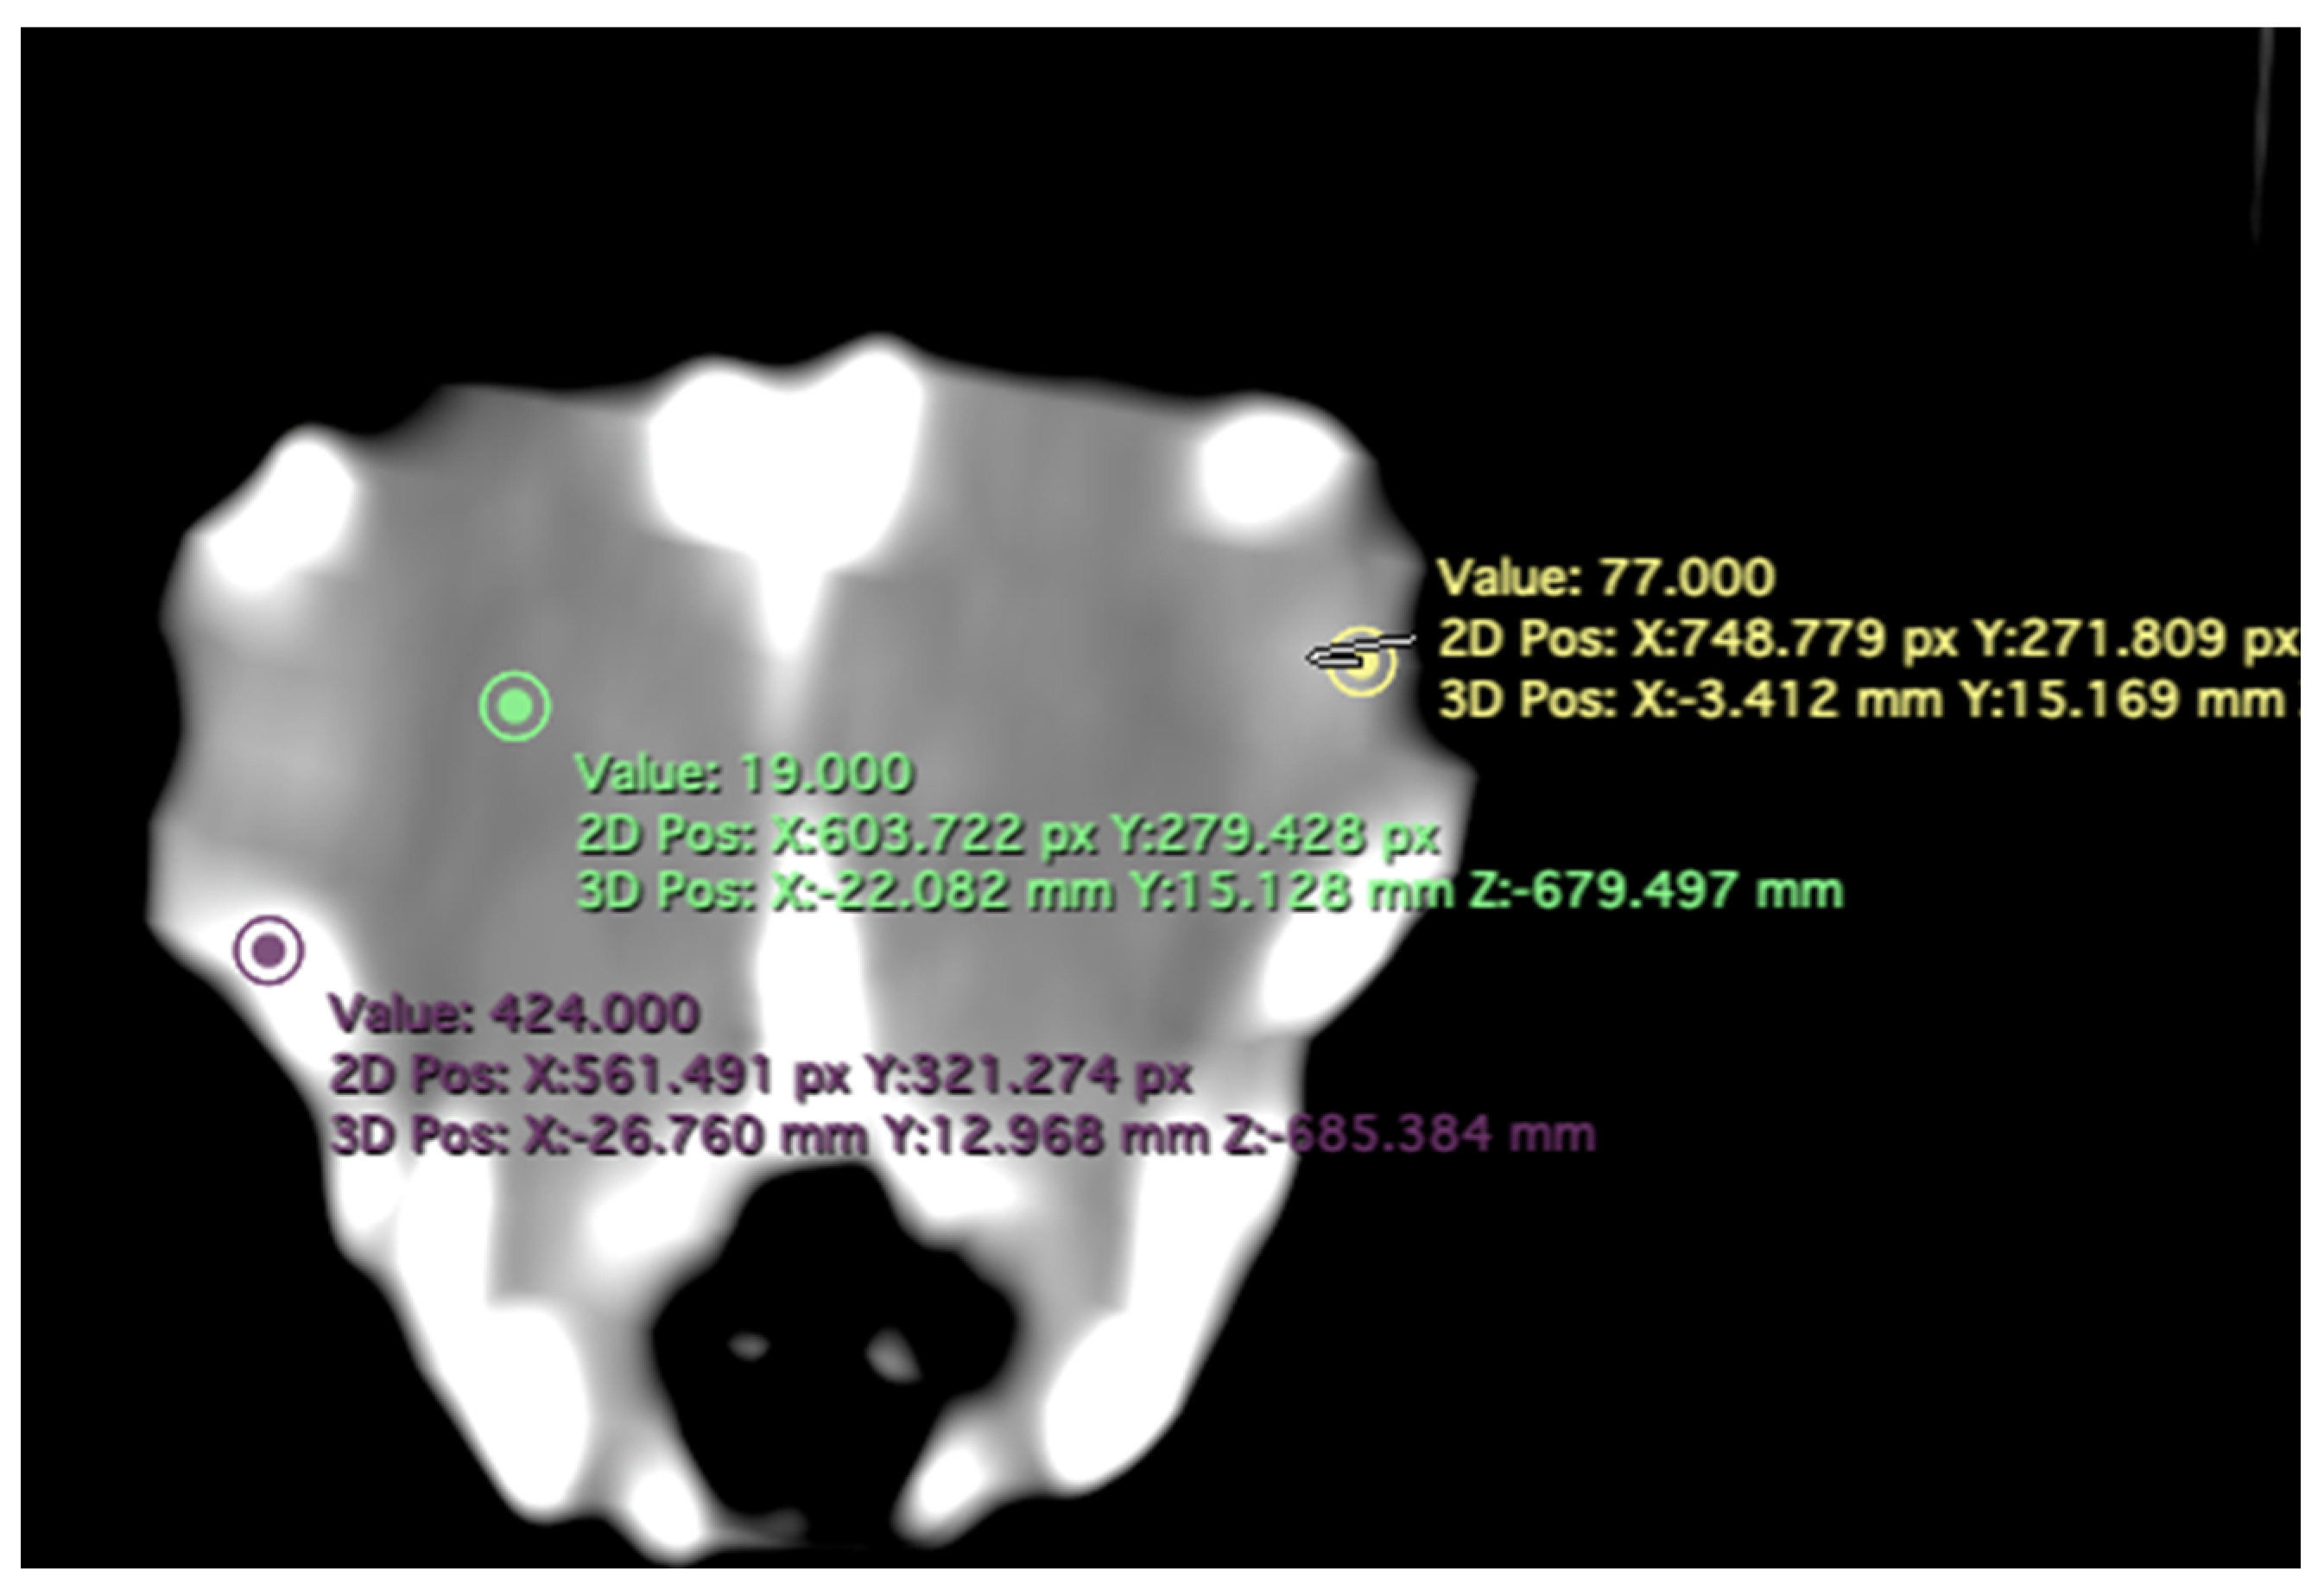

- Attenuation of the sclerotic ring and lens: This measurement was taken in the dorsal area and expressed in Hounsfield Units, providing information about the radiodensity of the sclerotic ring, lens, and vitreous humor (Figure 4).